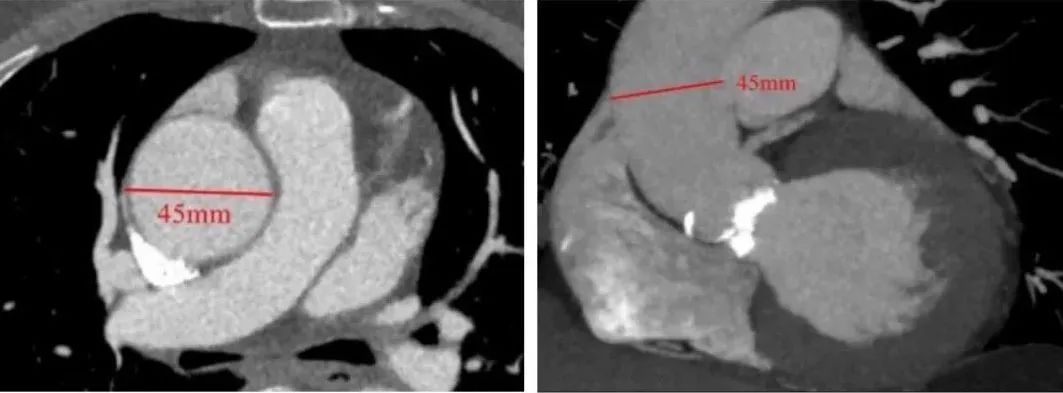

患者入院后完善相关检查,并给予药物支持治疗。术前检查我们发现患者先天性主动脉瓣二叶式畸形 主动脉瓣重度狭窄伴轻中度关闭不全,左室明显增大(LV 60),心功能测值降低(EF% 48%)(图1,2),同时合并升主动脉瘤样扩张(AAO 45)(图3,4)。心脏大血管外科胡佳教授对患者进行了全面的评估,反复与患者沟通手术相关风险和花费后决定为患者实施胸腔镜下肋间小切口免缝合主动脉瓣置换+升主动脉成形术。该方法既可以微创不损伤胸骨,免缝合主动脉瓣术中无需缝合打结,大大缩短体外循环和心脏阻断时间,降低手术风险,又可以在一定程度上降低患者总体费用。完善术前相关准备后手术如期进行。